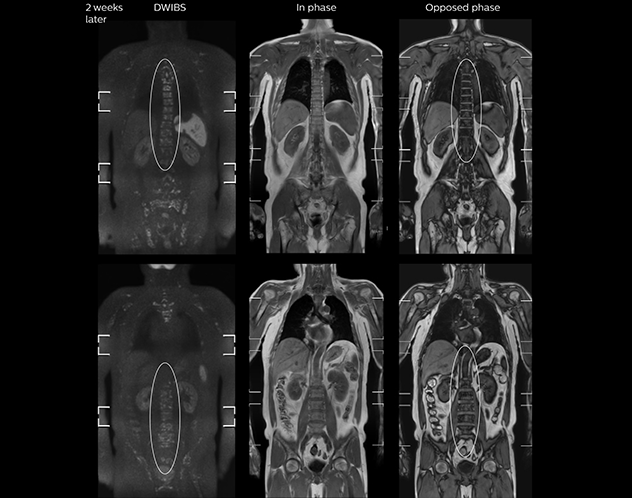

“In-phase and out-phase sagittal T1-weighted FFE images help us to visualize and further characterize bone lesions such as metastasis and bone-marrow hyperplasia that have high signal on DWI. These images are also used throughout radiotherapy, to monitor changes in the fatty bone marrow.”

After implementing the improved whole body protocol, the radiology team initially did not see a large increase in referrals, although Dr. Nobusawa saw clinical cases where the DWIBS images provided him valuable information for diagnosis. This is why Dr. Nobusawa and Mr. Naka started to actively educate referring physicians about the value of whole body DWIBS. They organized several presentations for physicians in the hospital, where they explained how DWIBS can be of value in oncology patients. The information it provides can be useful for physicians when staging cancer, as well as when determining or adjusting treatment strategy. Mr. Naka remembers some cases where DWIBS provided remarkable information. “In one example, DWIBS visualized bone lesions that could not be seen on PET or SPECT. In another case we had found a bone lesion when a normal L-spine scan for narrowing of the disk space was done. One extra DWIBS scan (2 stations, 8 minutes) demonstrated a lesion that later was confirmed to be the primary region of cancer.”